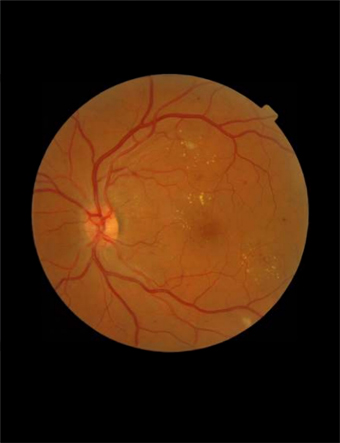

Fond d’œil et lésions les plus communes causées par la rétinopathie diabétique (hémorragies, micro-anévrismes, exsudats, nodules cotonneux), Deep Image Mining for Diabetic Retinopathy Screening, G Quellec et al. (2017) ©DR

La rétinopathie diabétique est une complication du diabète due à l’atteinte des vaisseaux de la rétine. Chez les personnes diabétiques, l’augmentation du taux de sucre dans le sang et ses fortes variations endommagent les capillaires rétiniens. A long terme, la vue est perturbée. En France, il s’agit de la première cause de cécité avant 65 ans. Deux tiers des patients diabétiques en sont atteints. La maladie est asymptomatique à ses débuts, et ce n’est qu’à un stade avancé que les symptômes apparaissent, d’où l’importance du dépistage qui représente un enjeu de santé publique. “Le problème de la rétinopathie diabétique est qu’elle est asymptomatique. Un patient peut avoir une rétinopathie diabétique avancée mais il voit bien car la zone centrale qui permet de voir net est préservée”, précise le Pr Aude Couturier. Selon les recommandations de la Haute Autorité de Santé, les personnes diabétiques doivent réaliser un fond d'œil tous les ans. Ce rythme peut être élargi à deux ans sous certaines conditions (notamment chez les diabétiques non insulino-traités et bien équilibrés).

Si le fond d'œil est un examen important pour le dépistage et le diagnostic de maladies ophtalmologiques, il permet également de voir les atteintes de la rétine dues à d’autres maladies, qui ne sont pas liées à l'œil. En effet, cet examen donne des indications précieuses sur l’état de santé général, comme l’explique le Pr Aude Couturier : “Il peut y avoir des maladies du fond d'œil qui font baisser la vision, surtout les maladies qui touchent la macula. Mais le fond d'œil est aussi le reflet d’autres pathologies. Il révèle par exemple l’état vasculaire du patient. Chez quelqu’un qui a de l’hypertension, on peut voir des modifications sur les fines artères rétiniennes. De la même manière, chez un patient diabétique, qui a un taux élevé de sucre dans le sang, on peut voir que les petits vaisseaux rétiniens sont endommagés et l’on observe des signes d’ischémie de la rétine. C’est un signe de rétinopathie diabétique”.